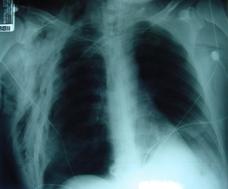

Pneumotorace sufocant bilateral Pneumotorace sufocant stang

Pneumotorace

sufocant stang Pneumotorace

sufocant drept Pneumotorace

sufocant drept